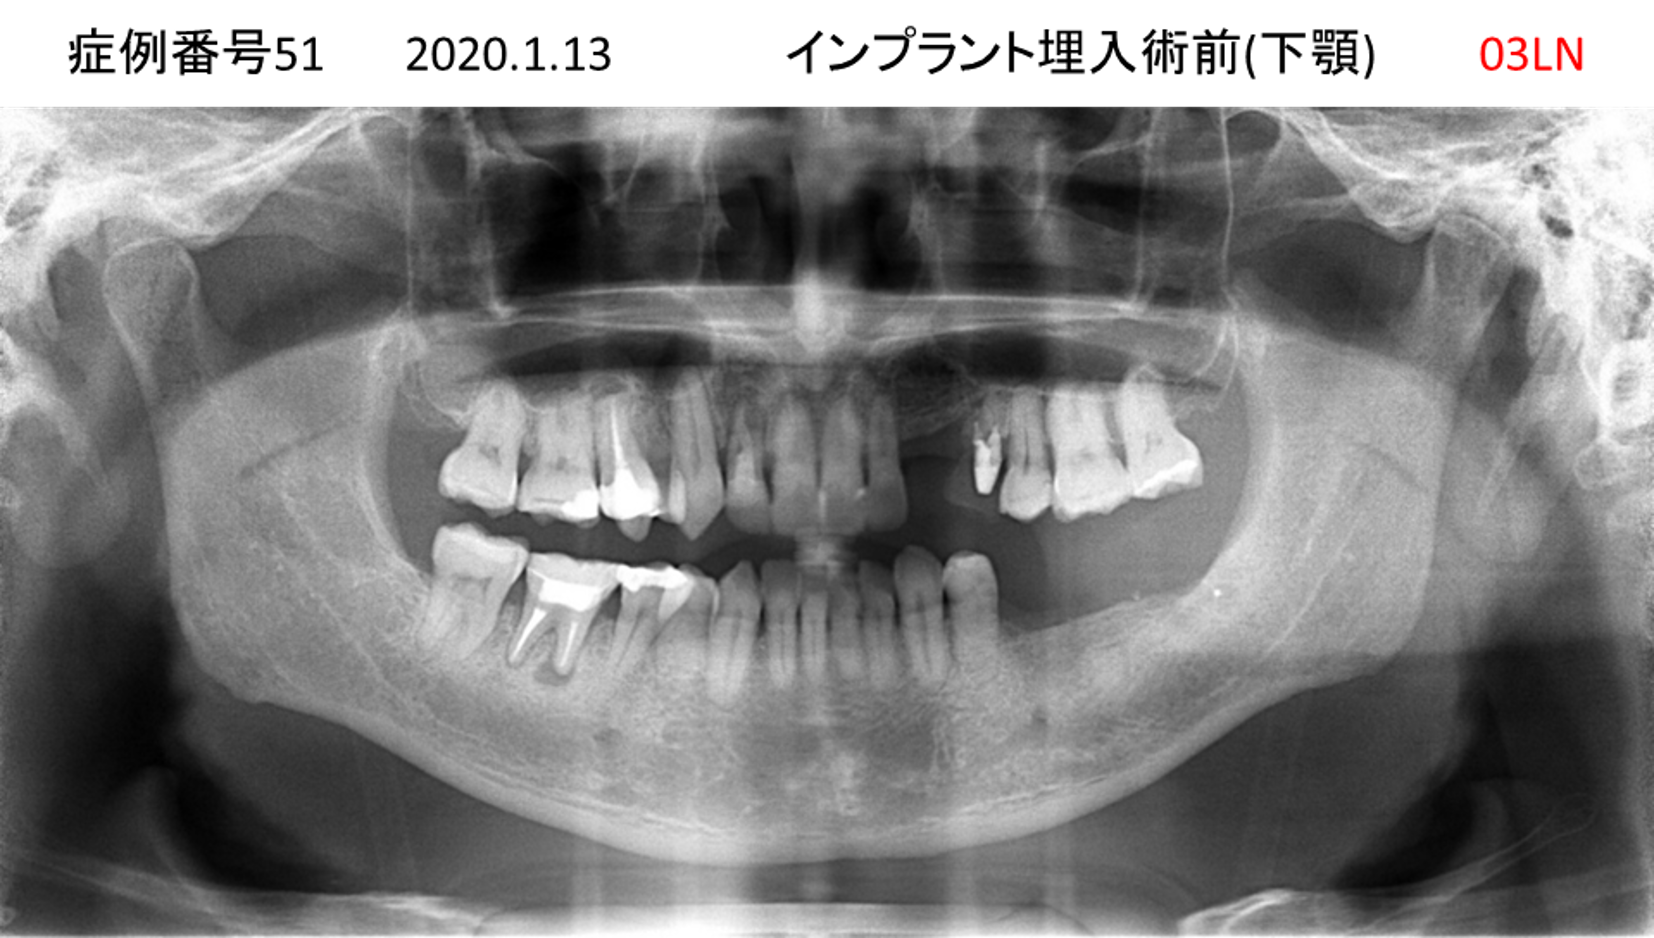

かめない/上の歯が揺れてきた患者様のインプラント症例

| 治療名称 |

インプラント |

| 治療費用 |

390万円+税 |

| 治療期間 |

6か月 |

| 患者さんの症状(主訴) |

かめない。上の歯が揺れてきた。 |

| 治療内容 |

サイナスリフト、抜歯即時インプラント |

| 治療結果 |

上の歯の揺れが収まった。噛めるようになった。食事がおいしい。 |

| 治療の注意点(リスク/副作用) |

インプラントが壊れたら再治療が必要 |